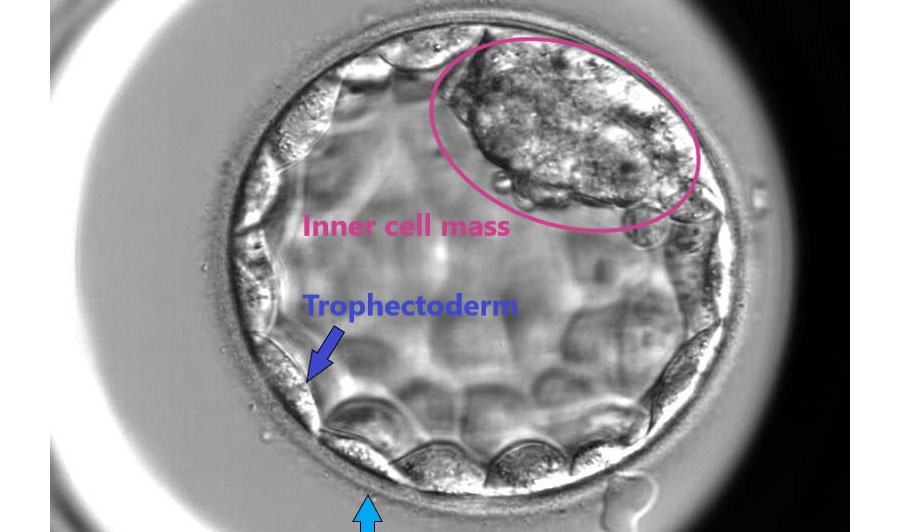

Embryo should achieve this stage to get implanted in the inner lining of the uterus,i.e, Endometrium. Blastocystconsistes of 100-200 cells which are arranged as :

1. Trophectoderm

2. Inner cell mass

Trophectoderm outermost layer have an importance in the implantation. Inner cell mass are the early cells of fetus.

When blastocysts are formed,grading system is used to define the grade of embryos.The grading is done depending on the following 3 characters

1. Inner cell mass

2. Trophectoderm.

3. The degree of expansion and size of the embryo.